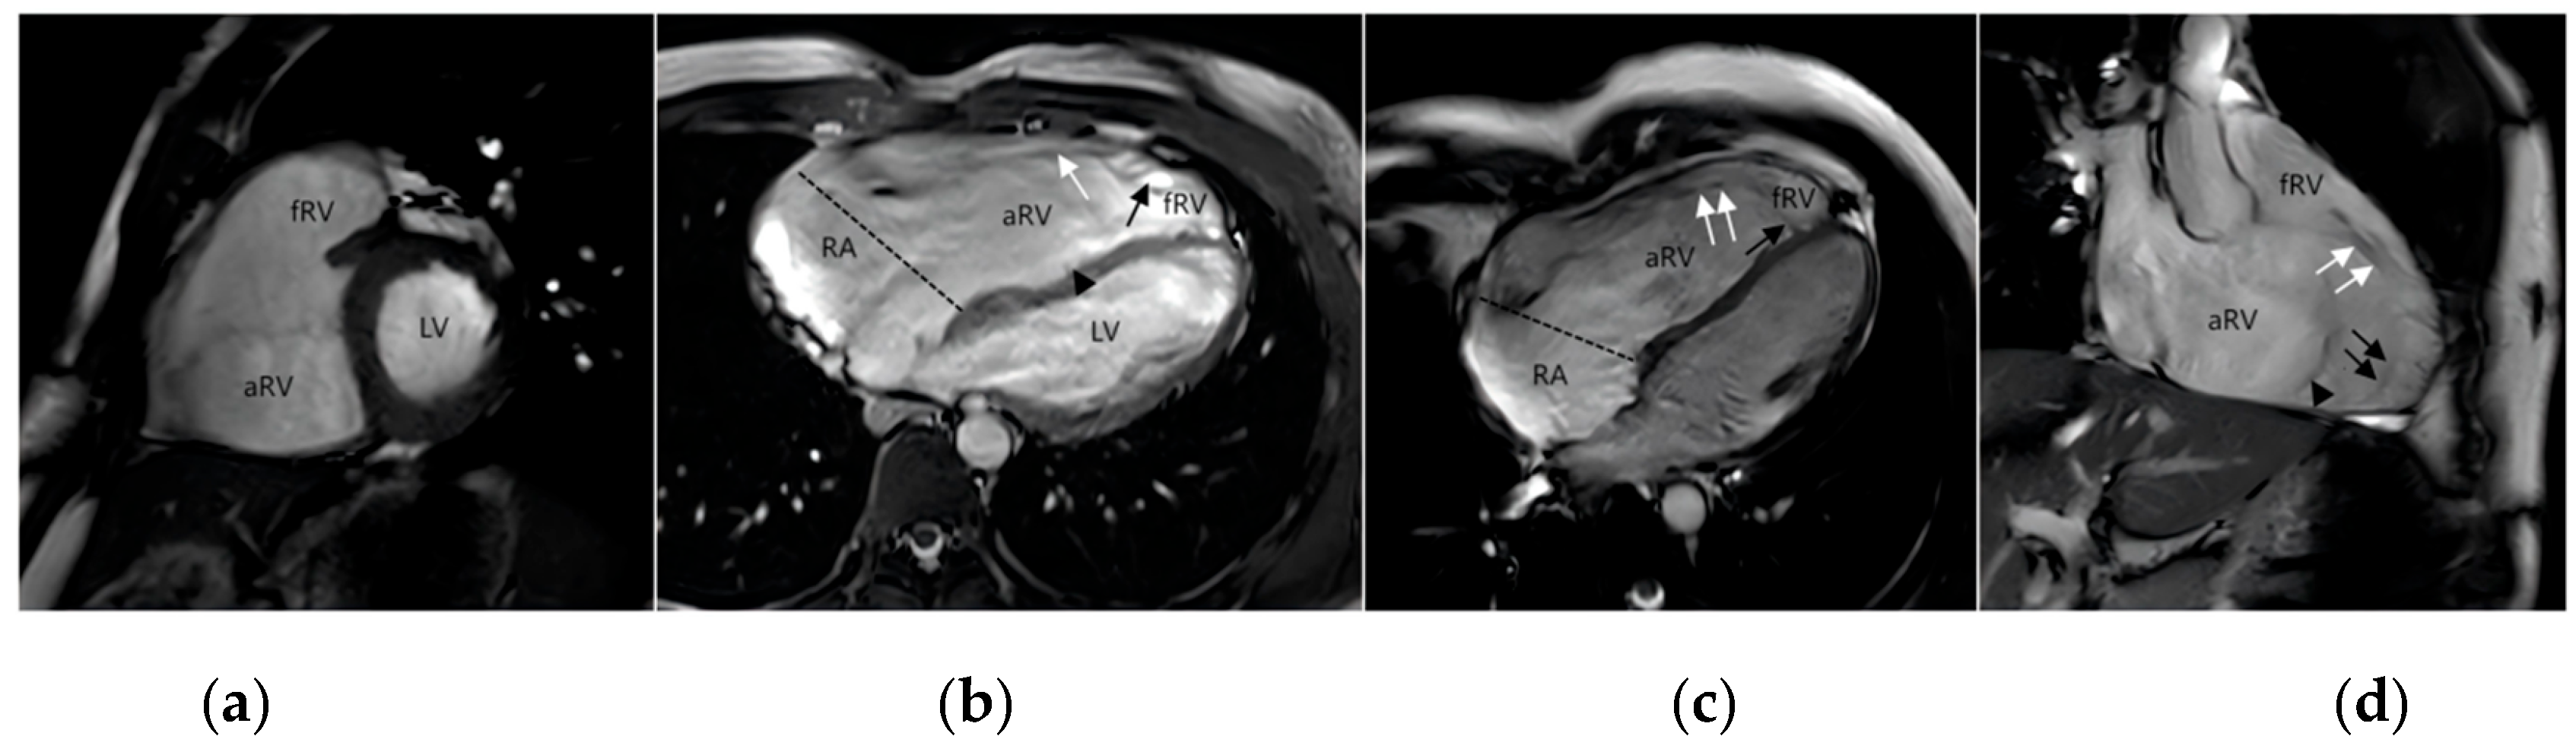

CMR was conducted using a 3.0T scanner. In cases where patients had multiple CMR scans, the most recent one before the Cone reconstruction was chosen for analysis, given its relevance to the current clinical state. Biventricular volumes were assessed at end-diastole and end-systole through manual delineation of the endocardial and epicardial contours. Right ventricular volume and functional results were reported in a 4-chamber stack, see Fig. 1 below. Classification criteria for right heart dysfunction was based on RVEF: Normal: RVEF ≥ 45%; Mild Dysfunction: RVEF 40%–44%; Moderate Dysfunction: RVEF 30%–39%; Severe Dysfunction: RVEF < 30%. Severe right heart dilatation is typically defined using the following criteria: right ventricular end-diastolic volume index (RVEDVi) ≥ 160 mL/m2 or right ventricular end-systolic volume index (RVESVi) ≥ 80 mL/m2. The Celermajer index was calculated as the right atrium plus the atrialized portion of the RV (functional RV þ left atrium þ left ventricle) from the four-chamber view. All CMR examinations were reviewed and contours were confirmed by a pediatric cardiologist with extensive CMR experience. The aforementioned procedures were independently performed by two experienced radiologists, with discrepancies resolved by consensus [16].

Figure 1: Magnetic resonance imaging of EA. (a) the short-axis image; (b) horizontal axis bitmap; (c) four-chamber heart view; (d) the inflow-outflow tract view of the right ventricle. The atrialized right ventricle (aRV) is located between the atrioventricular junction (dotted line) and the orifice of the functional tricuspid valve. Functional right ventricle (fRV) is the part of the right ventricle that lies between the aRV and the pulmonary valve. Anatomically, the right ventricle is a combination of aRV and fRV. The functional orifice of the tricuspid valve rotates toward the apex and upward toward the right ventricular outflow tract. Anterior valve (white↑), septal valve (black↑) and posterior valve (▲).